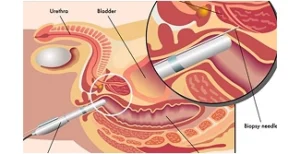

Exame diagnóstico guiado por ultrassonografia ou ressonância multiparamétrica, essencial para confirmação do câncer de próstata.